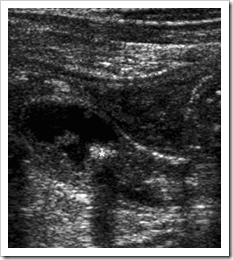

Ultrasound images Acute appendicitis. In transverse section, the appendix is round and measures 12 mm in diameter.